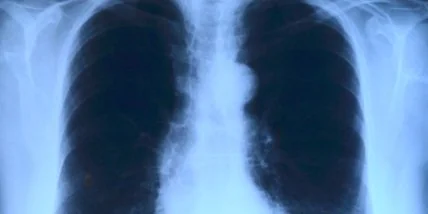

Дозы радиации в небольших количествах, такие как рентген, могут вызвать рак. К такому выводу пришла группа ученых-медиков Кембриджского университета в Великобритании.

Как пишет МедикФорум со ссылкой на релиз по результатам исследования, который опубликован на сайте MedicalXpress, ученые пришли к выводу, что малые дозы радиации также способны вызывать возникновение раковых опухолей, особенно на коже человека.

В исследовании, в частности, говорится, что рентген вызывает у человека мутации клеток в организме, которые ученые называют P53. Именно эти клетки отвечают за возникновение онко - заболеваний.

Ученые в ходе многочисленных опытов определили, что чем безопаснее уровни излучения, тем большее количество клеток подвергается мутации.

Если перед рентгенов ввести в организм антиоксиданты, то здоровые клетки начинают борьбу с испорченными клетками Р53. Но ученые предупреждают, что постоянное введение препаратов также может навредить и привести к большему распространению дефектных клеток.

Опасность гель-лака: как уберечьсяПо словам одного из авторов исследования, профессора Фил Джонса, отметил, риск компьютерной томографии и рентгена пока не изучен как следует, поэтому ученые продолжают исследования.